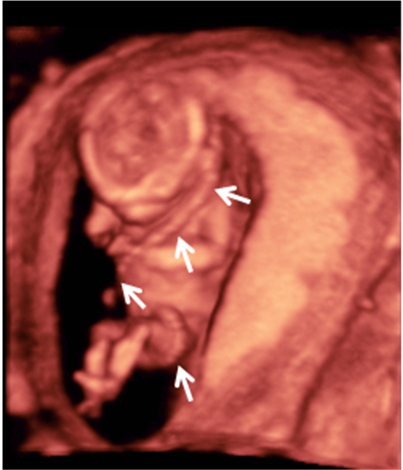

La ausencia de hueso nasal y tener un pliegue nucal aumentado son marcadores que se detectan en la ecografía de la semana 12 y que pueden significar que el feto padece alguna alteración cromosómica, como es el síndrome de Down.

Ecografía de hueso nasal ausente